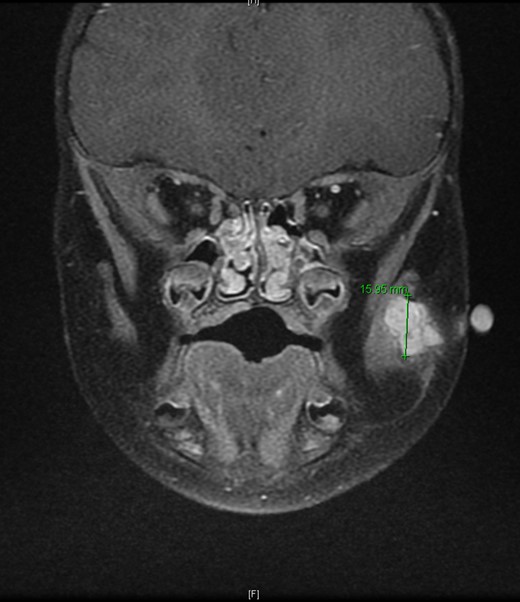

An 11-month-old male with a history of nasolacrimal duct stenosis and 4 mm thyroglossal duct cyst presented for evaluation of left facial swelling for 9 months. Approximately 6 months prior to admission, a mass was identified on the left cheek which had progressively increased in size over the past 2 months. The patient also had intermittent fevers the week prior to admission but was otherwise healthy. Baseline labs, including platelets, were within normal limits. On exam, he was found to have a firm, mobile, non-tender mass just inferior to the left zygomatic arch. Ultrasound revealed a vascularized solid lesion measuring 12 mm × 15 mm × 16 mm limited to the superficial soft tissues. MRI showed a multi-lobular mass with increased T2 signal centered within the left masseter and infiltrating signal in surrounding subcutaneous tissue (Fig. 1). The patient subsequently underwent ultrasound-guided core biopsy. The initial pathological diagnosis was consistent with TA, showing fibrovascular tissue containing compact nests of variably sized and ill-defined vascular channels. Immunohistochemistry staining showed the endothelial cells to be diffusively reactive for CD34 and CD31, partially reactive for D2-40, and negative for GLUT-1. However, upon further review, KHE was favored given the solid and infiltrative components on MRI, normal overlying skin on exam, and location of the lesion within subcutaneous fat. Accordingly, low-dose daily aspirin was prescribed prophylactically to prevent KMP. An MRI 2 months later, along with serial ultrasound images in the ensuing 26 months, showed no further growth (Fig. 2). His parents noted intermittent painless changes in size that did not seem to be related to any stimulus and returned to baseline size within hours. Surgical intervention at 3 years old is anticipated.

T2-weighted MRI revealed a homogenously enhancing 13 mm × 11 mm × 16.4 mm mass with indistinct margins centered within the left masseter muscle and protruding into the subcutaneous tissues laterally.